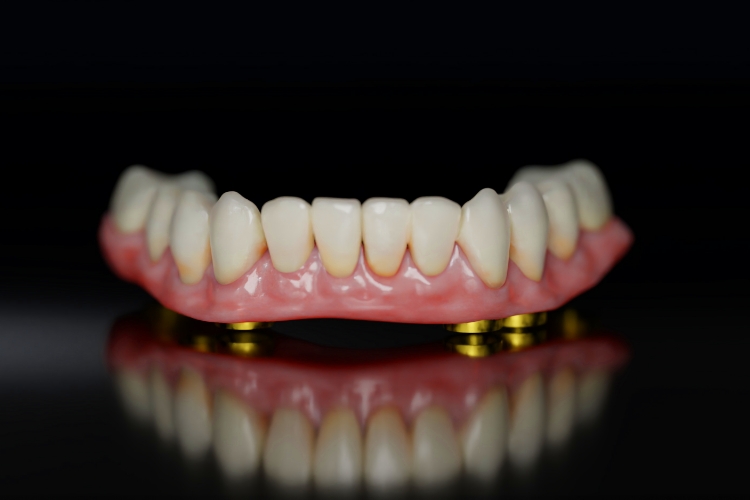

최종 보철물 장착

약 3~6개월 후 뼈와 임플란트가 완전히 결합되면 최종 보철을 장착합니다.

이후로는 본인 치아처럼 자연스럽게 사용할 수 있습니다. 임시 보철로 치료 기간 중에도

일상생활과 대인관계에 불편함이 적다는 점이 풀아치 임플란트의 큰 장점입니다.